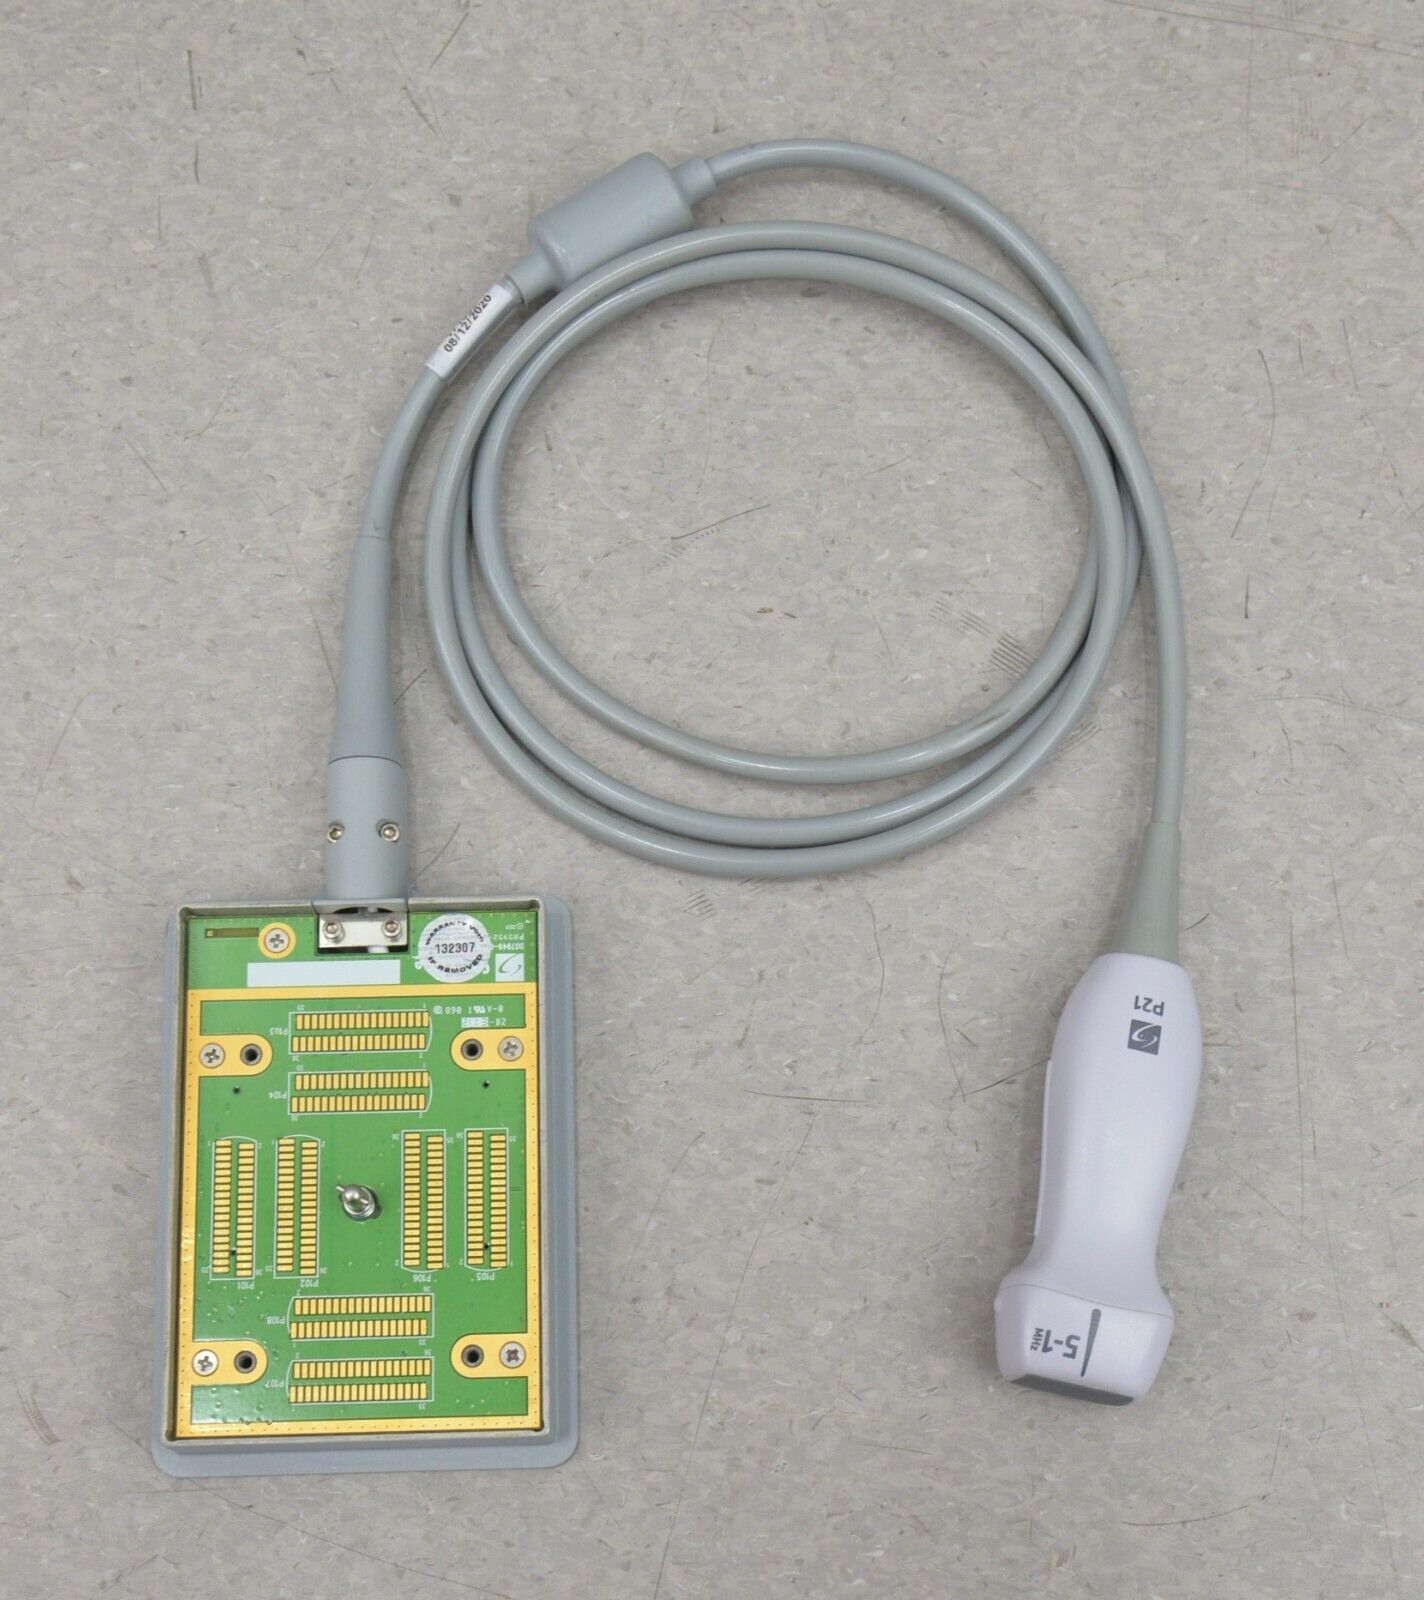

- Fujifilm Sonosite M-Turbo Ultrasound System W/ SonoSite P21x/5-1 MHz Transducer

January 15, 2025Fujifilm Sonosite M-Turbo Ultrasound System W/ SonoSite P21x/5-1 MHz Transducer

Fujifilm Sonosite M-Turbo Ultrasound System W/ SonoSite P21x/5-1 MHz Transducer

This Fujifilm Sonosite M-Turbo Ultrasound System W/ SonoSite P21x/5-1 MHz Transducer is in good working condition. This unit powers on properly and the display screen produces a clear picture. The buttons respond properly to selection and the connections are clean and in good condition. The battery holds a charge. There are a few minor scuff marks from previous use (see photos). This item comes with a 30 day satisfaction guarantee. Includes everything displayed in the photos and nothing else.